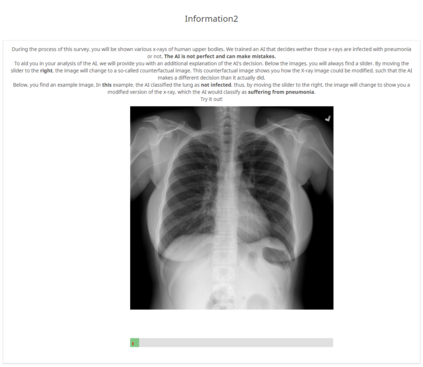

With the ongoing rise of machine learning, the need for methods for explaining decisions made by artificial intelligence systems is becoming a more and more important topic. Especially for image classification tasks, many state-of-the-art tools to explain such classifiers rely on visual highlighting of important areas of the input data. Contrary, counterfactual explanation systems try to enable a counterfactual reasoning by modifying the input image in a way such that the classifier would have made a different prediction. By doing so, the users of counterfactual explanation systems are equipped with a completely different kind of explanatory information. However, methods for generating realistic counterfactual explanations for image classifiers are still rare. Especially in medical contexts, where relevant information often consists of textural and structural information, high-quality counterfactual images have the potential to give meaningful insights into decision processes. In this work, we present GANterfactual, an approach to generate such counterfactual image explanations based on adversarial image-to-image translation techniques. Additionally, we conduct a user study to evaluate our approach in an exemplary medical use case. Our results show that, in the chosen medical use-case, counterfactual explanations lead to significantly better results regarding mental models, explanation satisfaction, trust, emotions, and self-efficacy than two state-of-the-art systems that work with saliency maps, namely LIME and LRP.